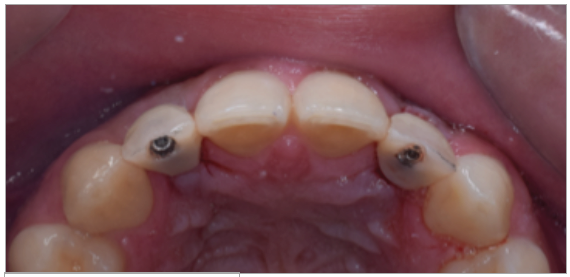

Paciente de sexo masculino de 24 años de edad, de raza mestiza, sin antecedentes sistémicos y oclusalmente estable, que fue transferido al servicio de Rehabilitación Oral del Posgrado y Especialización de la Universidad Peruana Cayetano Heredia, Lima, Perú. Recibió previamente tratamiento ortodóncico en el servicio de Ortodoncia y Ortopedia Maxilar por 6 años. Al examen intraoral presentó agenesia de las piezas 12 y 22 con evidencia de defectos óseos, presenta fenotipo periodontal grueso (figura 1). Al examen radiográfico se observa disminución generalizada de las raíces (Rizomicri), presenta ensanchamiento del ligamento periodontal generalizado (figura 2). Para el plan de trabajo para el diagnóstico se obtuvieron modelos de estudio primario, realizando el encerado para la planificación del tratamiento del sector anterosuperior. Al análisis tomográfico se evidenció poca disponibilidad ósea, motivo por el cual se planificó dos injertos en bloque de mentón con hueso particulado y plasma rico en plaquetas previo a la colocación de implantes dentales (figura 3 y figura 4). Pasado el tiempo de osteointegración (6 meses) se colocaron dos implantes Strong WS Cono Morse (SIN®, Sao Paulo, Brasil) de 3.5 mm x 11 mm. En la segunda fase, se confeccionaron provisionales de acrilico termocurado Vitalloy® (Vitacryl; A. Tarrillo Barba S.A., Lima, Perú) para el manejo de los tejidos blandos a nivel de las piezas 12 y 22, los cuales estuvieron fijados a un cilindro provisional de titanio (SIN®, Sao Paulo, Brasil) atornillado al implante, verificando la adaptación de este al implante mediante una radiografía periapical (figura 5). El cilindro fue recortado dando una altura de 6 mm, los provisionales fueron agujerados en el medio (figura 6), de tal forma que el cilindro calce en el medio del espacio edéntulo, se cubrió la entrada del cilindro con teflón (Golfo USA®) y se capturó el cilindro con acrílico de autocurado Duralay color 62 (Reliance Dental Manufacturing LLC, Illinois USA) (figura 7). Después del acrilizado se retiró el provisional, en la parte cervical se realizó un incrementó con resina fluida (Filtek™ Z350XT Flow - 3M ESPE Dental Products. St. Paul, Minnesota, USA) formando el contorno crítico a 2mm por debajo del zenit de los incisivos centrales de tal manera que entre los zenits de los incisivos centrales, laterales y caninos formen una zona triangular. El contorno subcrítico se realizó de forma convexa (figura 7 y figura 8). Se finalizó con el acabado y pulido del provisional con gomas de grano grueso (gris) y grano fino (verde) (Politip, Ivoclar-Vivadent; Schaan, Liechtenstein). Se manejó la conformación de los tejidos blandos en 2 citas mediante la adición por capas de resina compuesta (Filtek™ Z350 - 3M ESPE Dental Products. St. Paul, Minnesota, USA) a nivel del contorno crítico y subcrítico a las 2 semanas y 4 semanas de la instalación del provisional (figura 9 y figura 10). Se logró conformar las papilas interdentales, el contorno crítico y subcrítico observando que los tejidos se encontraran estables, sin inflamación, con el color de la encía igual a la encía adyacente; todo esto nos indicó que se podía realizar la impresión definitiva. La instalación final se realizó con coronas metal cerámicas cementadas (figura 11 y figura 12).